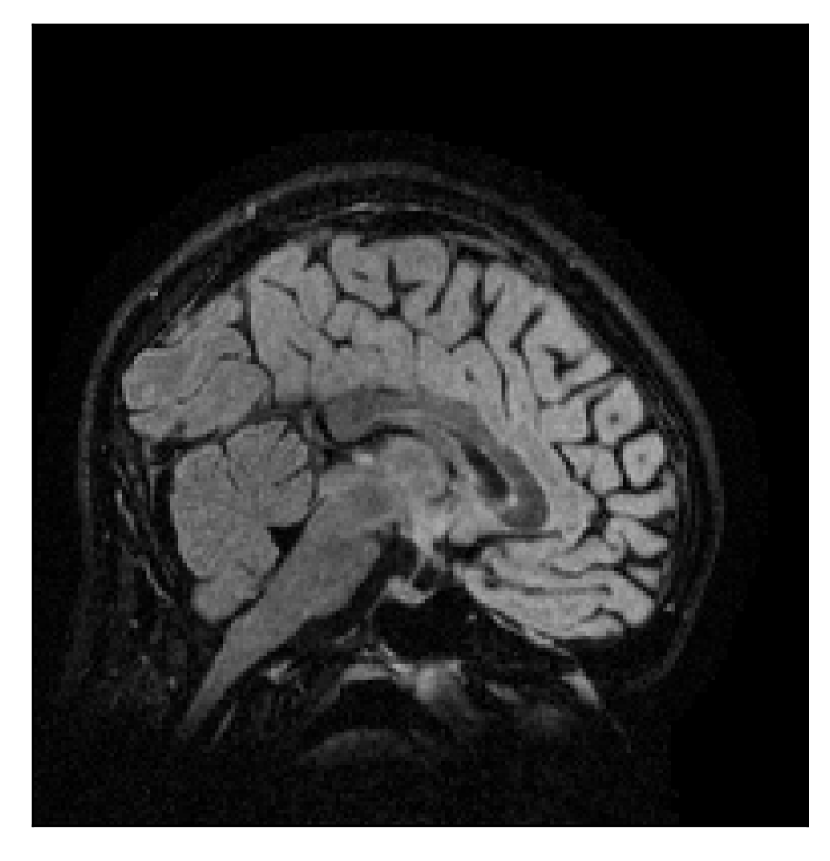

We consider three levels of motion corruption: (i) the volunteer moves once, (ii) the volunteer moves twice, and (iii) the volunteer moves five times. The volunteer is instructed to change its head position every time it is prompted to do so, and maintain that position in between instructions. We use T2-FLAIR-weighted contrasts as corrupted scans, with T1-weighted contrast as a reference (see Table 1 for further details). The corrupted acquisition employs randomized sampling.

| Section 3.1, Figure 2 | Sagittal | 23.94 | 27.95 | 0.7068 | 0.7936 |

| Coronal | 26.66 | 29.82 | 0.7653 | 0.8332 | |

| Axial | 25.40 | 30.16 | 0.7616 | 0.8490 | |

The motion-corrected full-volume scans were analyzed by a neuroradiologist with 16 years of experience. These were generally deemed of good radiological quality. The motion-related artifacts have been completely removed, and the results are quite close to the ground truth. In Table 3, we organized a more detailed qualitative analysis of the 3D results, geared toward a radiological assessment of the corrected scans.

| Experiment | Contrast | Motion resolution | Blurring | Artifacts | Additional comments |

| Section 3.1, Figure 2 | T2-FLAIR | Completely corrected | Some blurring | No additional artifacts | Good grey white matter differentiation |

4.1 Experiment 1: robustness test

We gather the results for the robustness test described in Section 3.1 (volunteer 1) in Figures 2, 4, and 6 for motion corruption mechanisms associated to one, two, and five changes of position, respectively. Furthermore, we juxtapose the corrected images with varying degrees of corruption in Figure 8. We observe that the proposed method consistently ameliorates the corrupted scan. The quality indexes based on PSNR and SSIM show only a modest decrease in correction quality as a function of motion complexity (Figure 8).

Our experimentation based on volunteer data aimed at assessing the robustness of the correction quality with respect to motion artifacts of increasing complexity. In this study, we equated this complexity to the number of volunteer changes of pose during the acquisition phase. Clearly, this does not fully describe the complexity of motion encountered in practice in the clinic, but it only constitutes a preliminary step in that direction. Nevertheless, the results described in Section 4.1 support the indication that the retrospective motion correction of T2-FLAIR weighted images based on a T1 reference contrast is quite robust in terms of reconstruction quality, with only minor degradations in terms of contrast and resolution.

Sagittal

Coronal

Axial

Axial detail